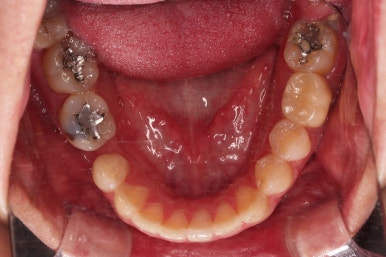

초진 시 입안의 모습입니다.

화살표는 결손 부위, 동그라기믄 유치잔존과 매복치아 부위입니다.

아래 어금니쪽은 선천결손이었고요.

동그라미는 유치가 있는 상황이었는데요. 잇몸도 많이 파괴되어 있었고, 유치 자체의 상태도 좋지 못했어요.